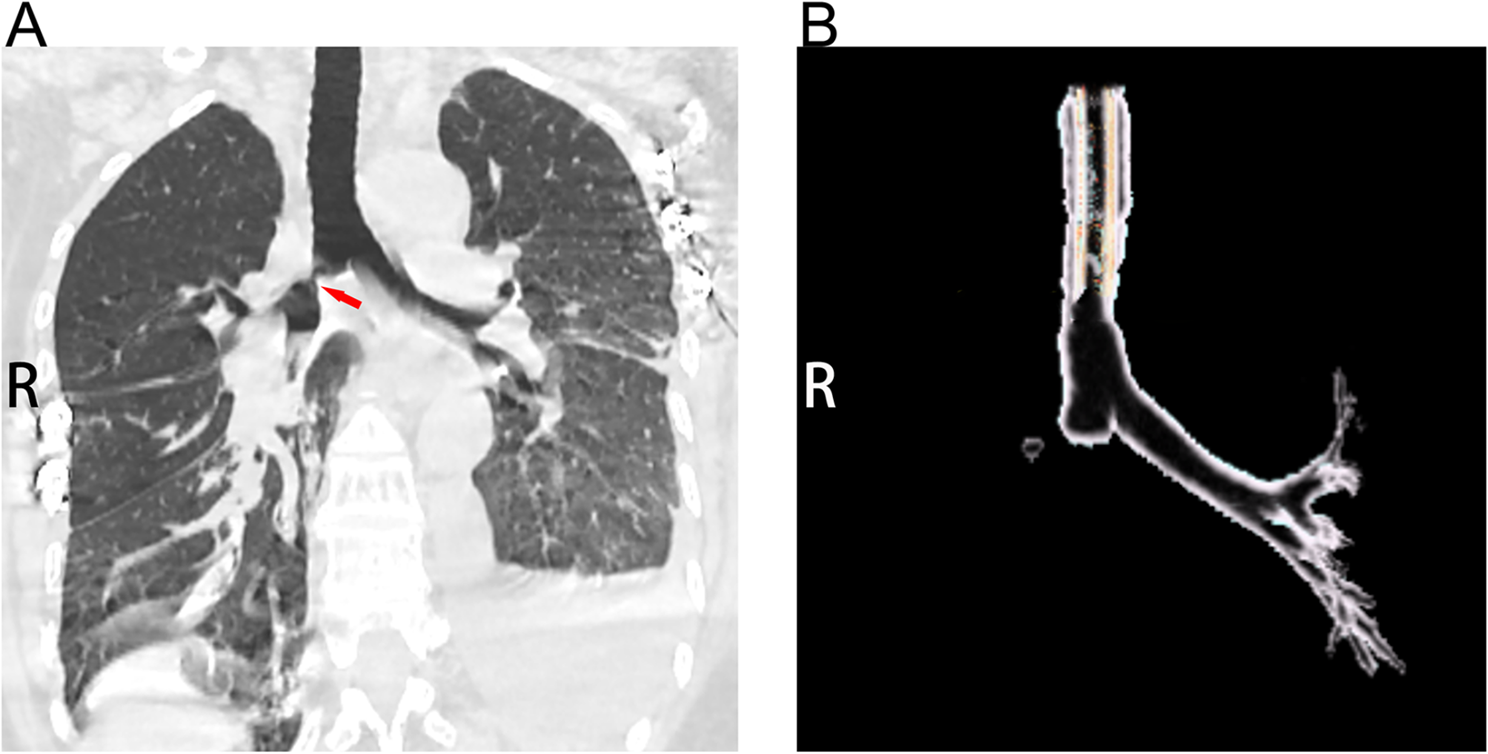

Fig. 1

Four anatomical models of BAV anatomical models were established. (A) The diameters of the ascending aorta (AAo) are 4.0 cm, 4.5 cm 5.0 cm and 5.5 cm, respectively; while, the size and the appearance of other parts are fixed; (B) Regions of interest where the hemodynamics were analyzed